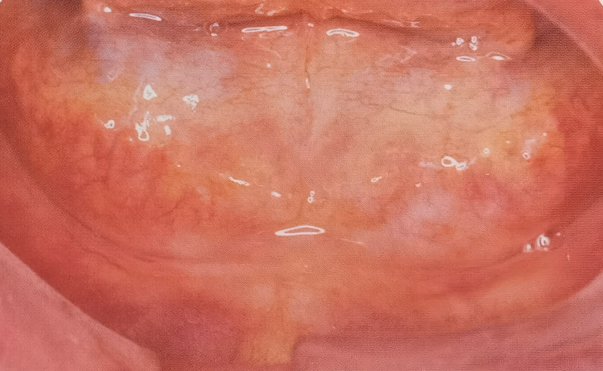

3.一类至四类无牙合口内像

2.从左至右分别为一类至四类无牙颌,牙槽骨逐渐吸收